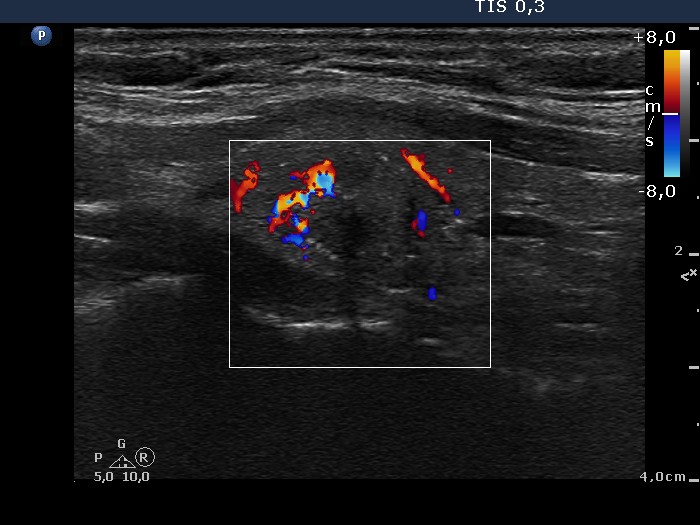

The echogenicity of the nodule - case conp 047 (ultrasonographic picture 7)

Lower part of the left lobe, longitudinal scan, color Doppler mode. The lesion presents an irregular vascular pattern.